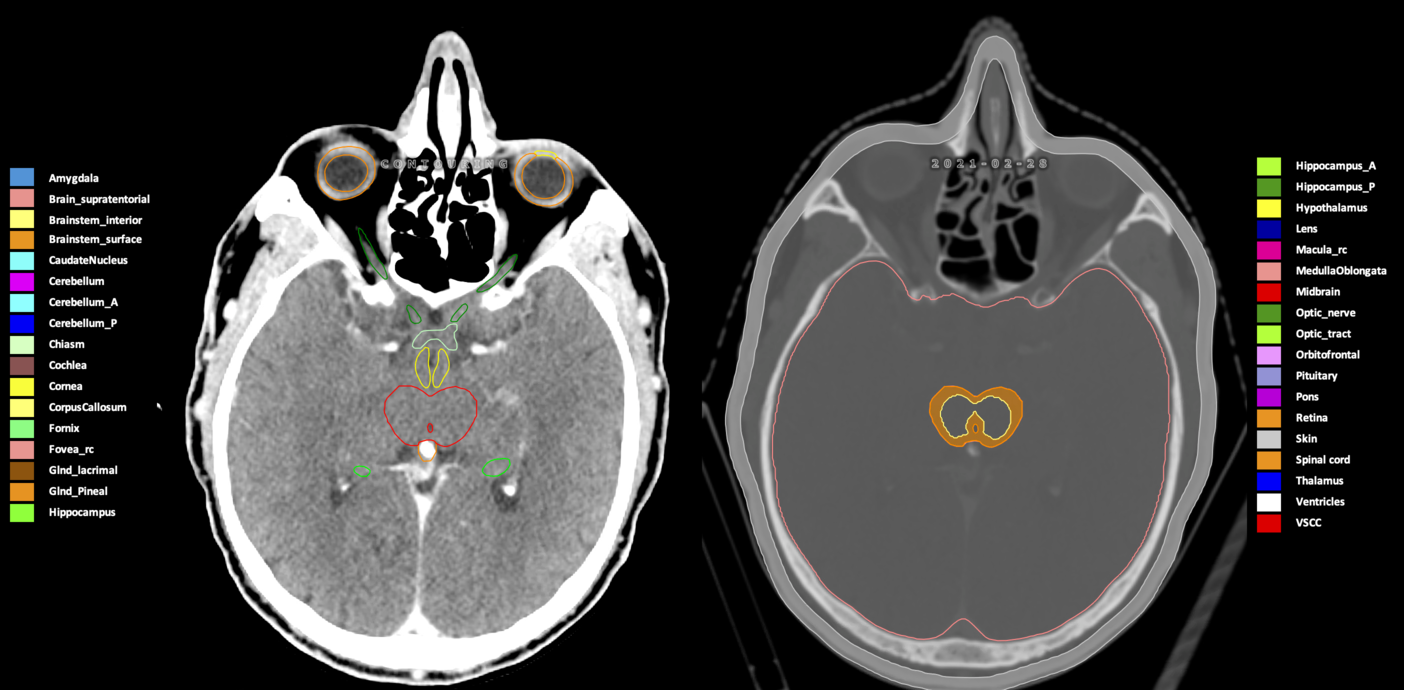

Included are all OARs known to be relevant for radiation-induced toxicity in neuro-oncology: brain, brainstem (midbrain, pons, medulla oblongata), chiasm, cerebellum (anterior & posterior), cochlea, cornea, hippocampus (anterior & posterior), hypothalamus, lens, lacrimal gland, optic nerve, pituitary, skin, and vestibular & semicircular canals. To further facilitate research on cognition, vision and radiological changes after irradiation of the brain, potential clinically-relevant OARs are included: amygdala, caudate nucleus, cerebellum (anterior & posterior), corpus callosum, fornix, macula, optic tract, orbitofrontal cortex, periventricular space (PVS), pineal gland, and thalamus.

Three-dimensional delineation of the 25 consensus OARs for neuro-oncology are shown on CT (WW/WL 120/40, 3000/600), 3T MR images, (T1Gd, T2FLAIR 1mm) and 7T MR (MP2RAGE 0.7 mm). All are presented in transversal, sagittal and coronal view.